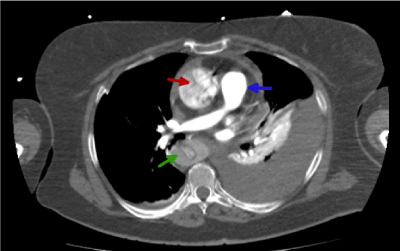

Figure 4, shows additional information. This includes; (i) a hypo-enhanced aortic flap present in the descending aorta (green arrow); (ii) the dissection of the entire intima allows us to observe a circumferential intimal flap and a narrow true lumen in a filiform shape (green arrow)7; (iii) the red arrow also shows a typical cobweb sign distribution. The appearance of this distribution is a clear sign of false lumen [8]; (iv) hiperenhanced pulmonary artery (blue arrow).

Figure 4. Thoracic CT image with i.v.c. in arterial phase that shows the dissection and the false lumen (green arrow)